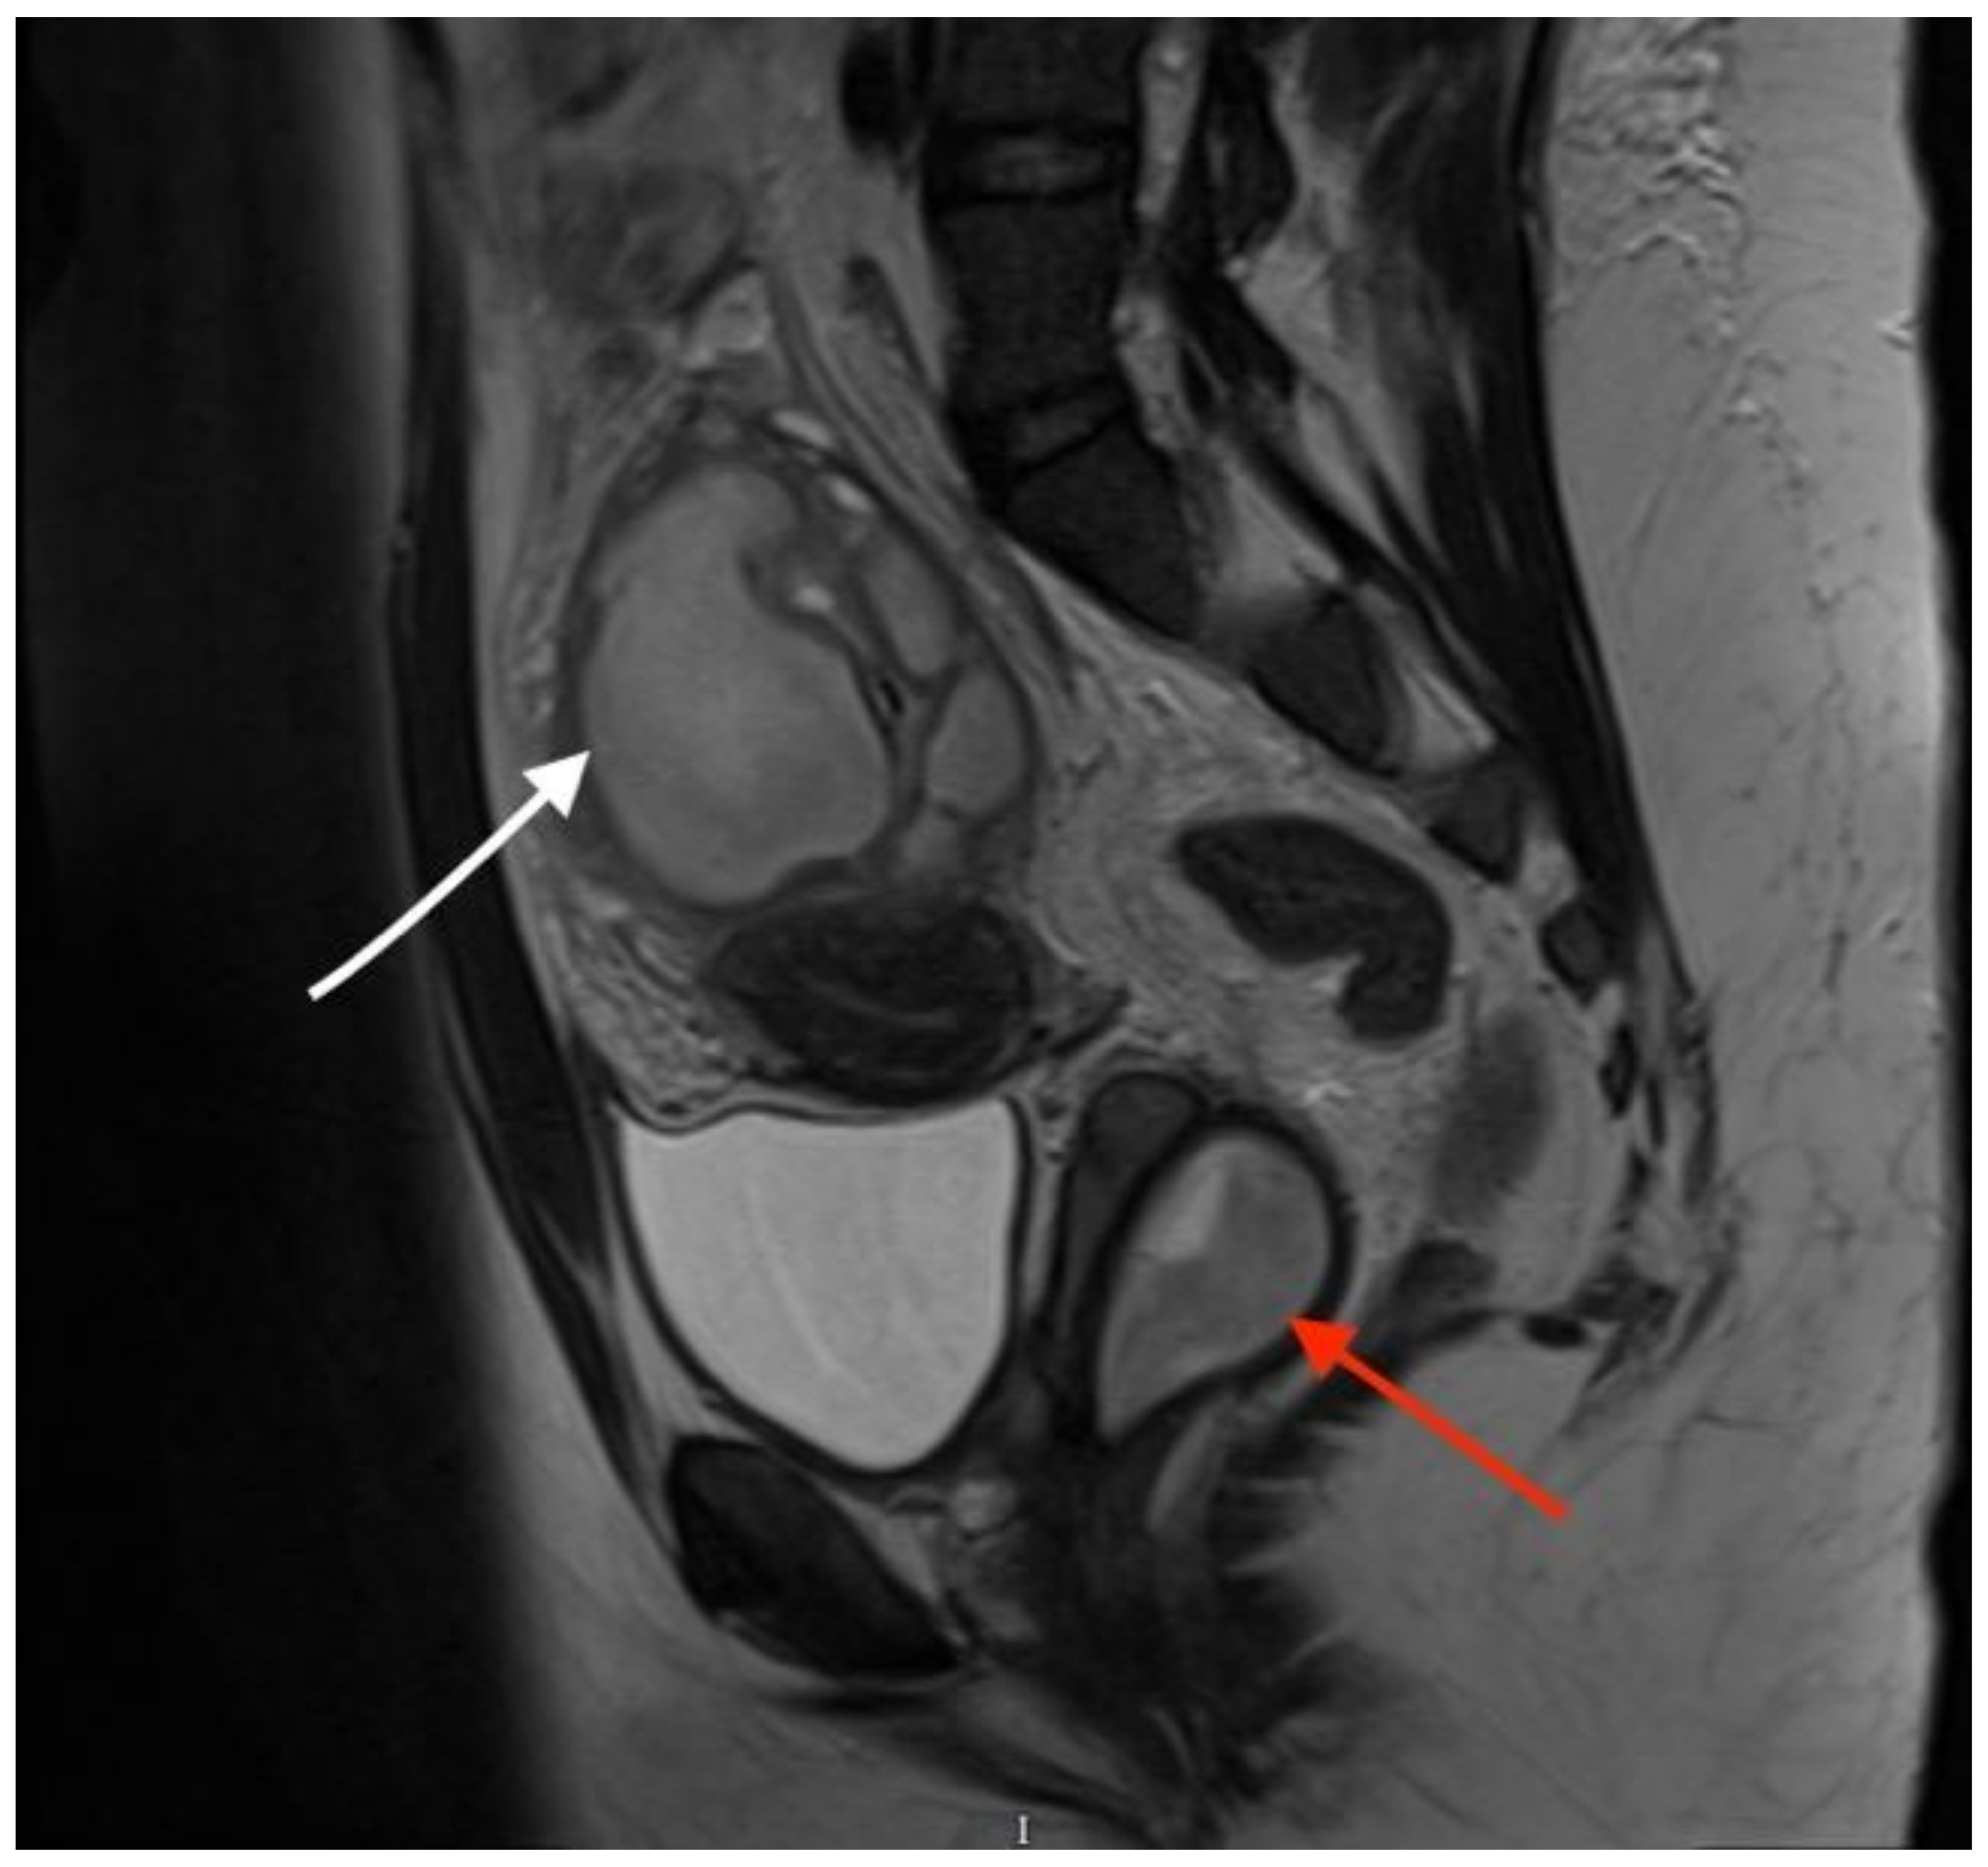

Coronal T2-weighted MR image shows 2 cervical canals (White arrow indicates the two cervical canals. The right-sided cervix leads to the obstructed haematopyocolpos). OHVIRA syndrome, also known as Herlyn–Werner–Wunderlich syndrome, is a rare uterine and renal congenital abnormality which is characterized by an obstructed hemivagina and ipsilateral renal agenesis [2]. The exact prevalence of the syndrome has not been yet estimated, but it has been reported that it accounts for 0.16–10% of Mullerian abnormalities, the incidence of which is 2–3% of the population [3]. Assessment via pelvic ultrasound in combination with MRI helps to establish an accurate clinical diagnosis [4]. In the majority of cases, pubertal women are more likely to be identified with the syndrome, since the onset of menstrual periods might lead to hematometra and/or delayed menarche. However, in cases of partial obstruction, the diagnosis can be elusive, often taking years to be established, leading, at times, to women presenting in adulthood with symptoms resembling pelvic infection and endometriosis [2]. Septectomy remains the treatment of choice and should be performed in all affected patients. Knowledge of this rare condition and maintaining high levels of suspicion is critical in these cases [5,6].